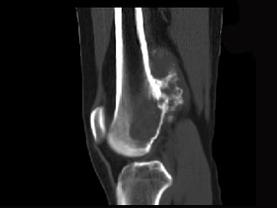

男,34岁,大腿下段疼痛2年,可摸到肿块,请结合所提供图像,选择最佳选项 ( )A、纤维肉瘤B、巨细胞瘤C、软骨肉瘤D、软骨瘤...

问题 男,34岁,大腿下段疼痛2年,可摸到肿块,请结合所提供图像,选择最佳选项 ( )

选项 A、纤维肉瘤 B、巨细胞瘤 C、软骨肉瘤 D、软骨瘤 E、骨肉瘤

答案 C